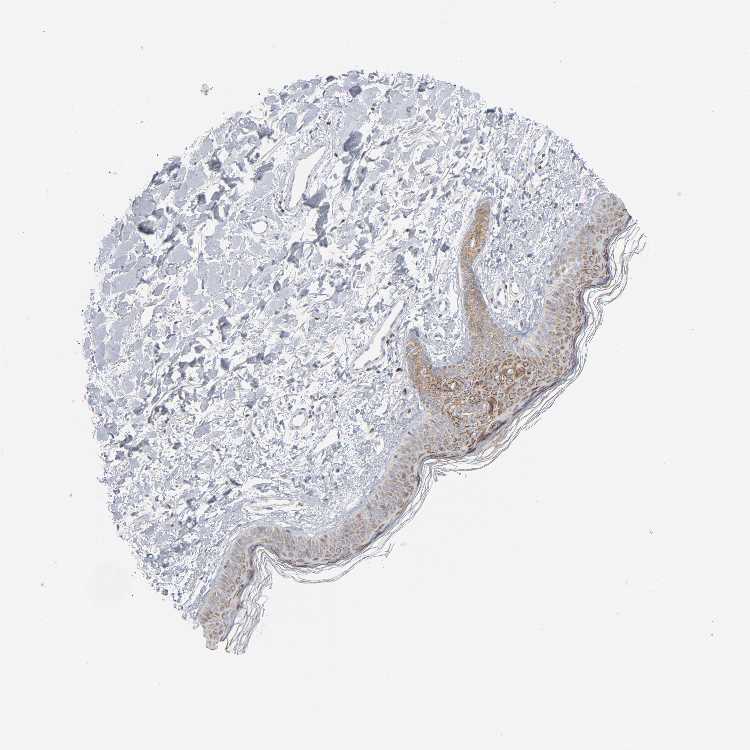

SKIN 2 - Antibody stainingi

Antibody staining in the annotated cell types in the current human tissue is reported as not detected, low, medium, or high, based on conventional immunohistochemistry profiling in selected tissues. This score is based on the combination of the staining intensity and fraction of stained cells.

Each image is clickable and will lead to virtual microscopy that enables deeper exploration of all samples and also displays staining intensity scores, fraction scores and subcellular localization as well as patient and tissue information for each sample.

Antibody CAB004222Antibody CAB005126

Cells in basal layer High-

Cells in corneal layer Medium-

Cells in granular layer High-

Cells in spinous layer High-

Endothelial cells Medium-

Epidermal cells -High

Extracellular matrix Not detected-

Fibrohistiocytic cells Medium-

Langerhans cells High-

Lymphocytes Not detected-

Melanocytes Not detected-

Vascular mural cells Not detected-